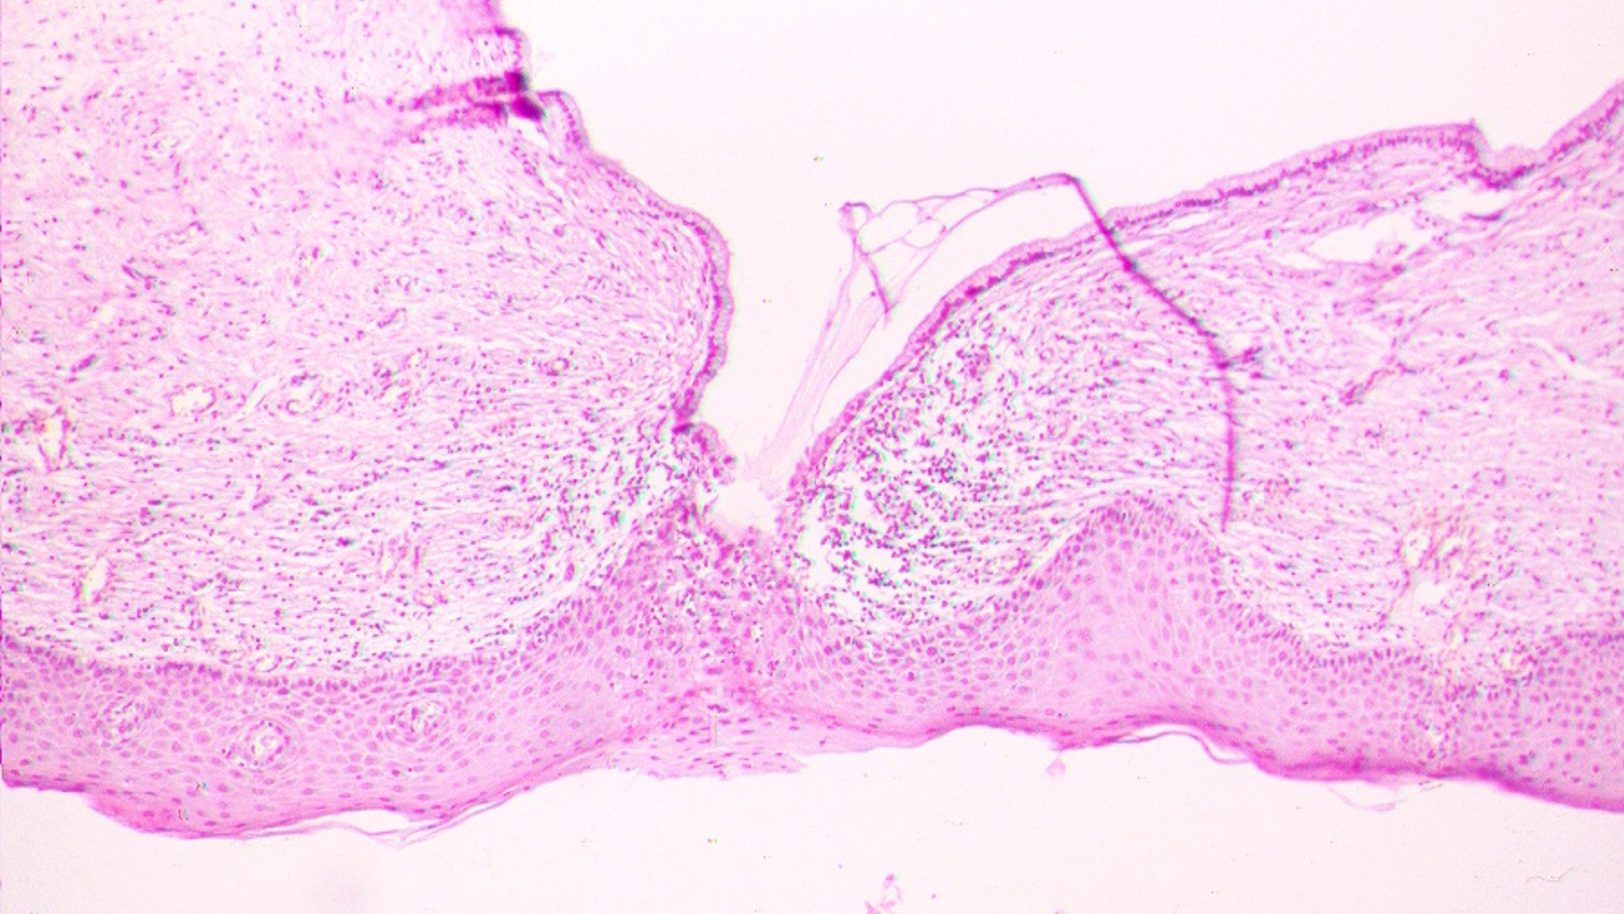

Histologija – tai yra laboratorinis tyrimas, kurio metu mikroskopu apžiūrimi žmogaus audiniai ir organai. Histologija remiasi preparatais, gautais atliekant tokias procedūras kaip endoskopiją, kolonoskopiją ir kolposkopiją arba atliekant chirurgines operacijas.

Histologinį tyrimą atlieka gydytojas patologas, jam padeda laborantas, kuris paruošia preparatą ištyrimui (atliekami pjūviai, paruošiami stikleliai). Tada preparatas gali būti veikiamas dažais ir kitais metodais, kad būtų išryškintos, atskirtos ar pašalintos ląstelės ir jas būtų galima geriau apžiūrėti mikroskopu.